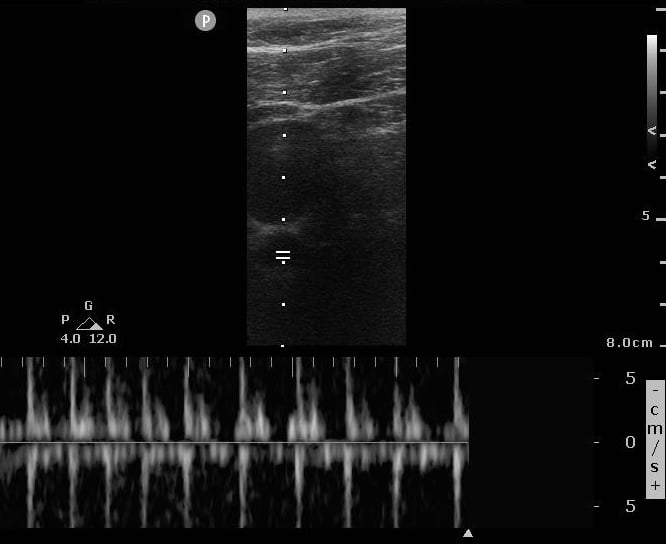

Case 1, Image 2.

Sustained regular Doppler pulsations during the pause, indicated ROSC. Image courtesy of Yale School of Medicine, Emergency Department.